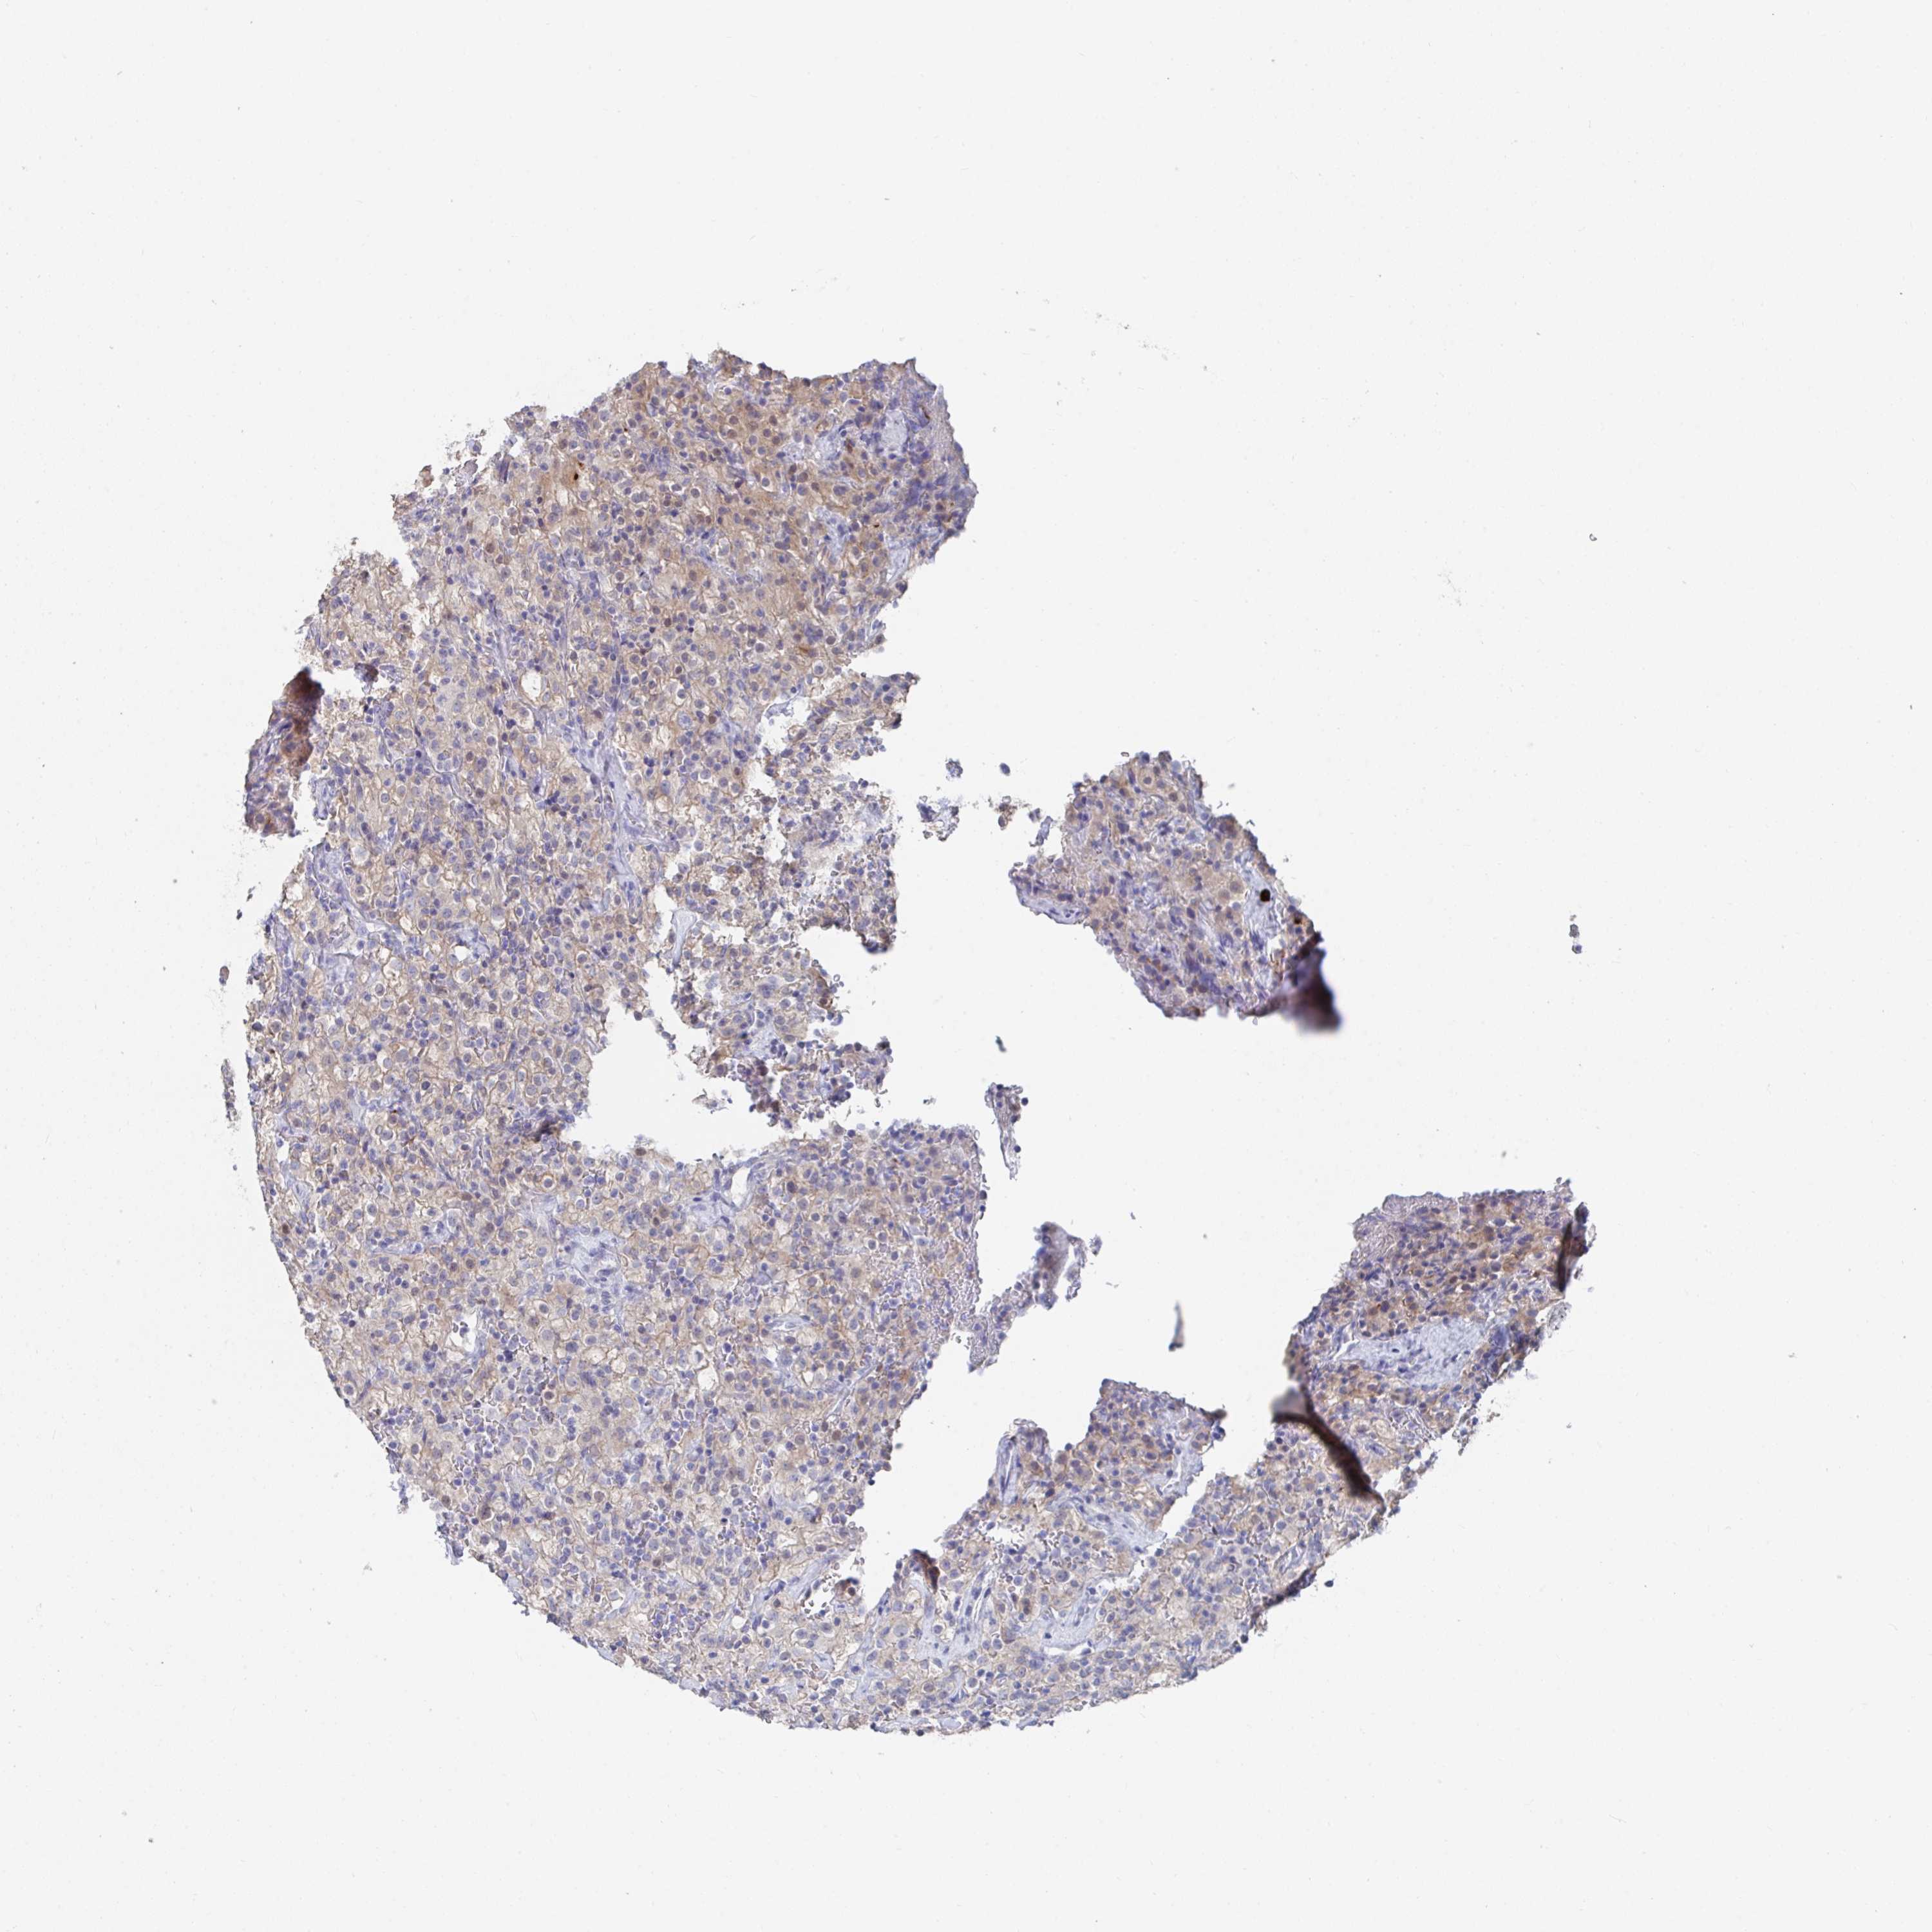

KIDNEY RENAL CLEAR CELL CARCINOMA (VALIDATION) - Interactive survival scatter ploti

The Survival Scatter plot shows the clinical status (i.e. dead or alive) for all individuals in the patient cohort, based on the same data that underlies the corresponding Kaplan-Meier plots. Patients that are alive at last time for follow-up are shown in blue and patients who have died during the study are shown in red.

The x-axis shows the expression levels (FPKM) of the investigated gene in the tumor tissue at the time of diagnosis. The y-axis shows the follow-up time after diagnosis (years). Both axes are complimented with kernel density curves demonstrating the data density over the axes. The top density plot shows the expression levels (FPKM) distribution among dead (red) and alive patients (blue). The right density plot shows the data density of the survived years of dead patients with high and low expression levels respectively, stratified using the cutoff indicated by the vertical dashed line through the Survival Scatter plot. This cutoff is automatically defined based on the FPKM cutoff that minimizes the p-score. The cutoff can be changed by dragging the vertical line or by entering a cutoff value in the square labeled "Current cut-off".

Under the Survival Scatter plot the p-score landscape (black curve; left axis) is shown together with dead median separation (red curve; right axis). Dead median separation is the difference in median mRNA expression between patients who have died with high and low expression, respectively. It is calculated as follows: median FPKM expression of dead patients with high expression - median FPKM expression of dead patients with low expression. This is intended to aid the user in visually exploring custom cutoffs and the associated p-scores and dead median separation.

Individual patient data is displayed and can be filtered by clicking on one or more of the category buttons on the top of the page. Categories describing expression level and patient information include: high, low, alive, dead, female, male and tumor stages. The scale of the x-axis can be toggled between linear and log-scale by clicking on the "x log" button. Mouse-over function shows TCGA ID, patient information and mRNA expression (FPKM) for each patient.

& Survival analysisi

Kaplan-Meier plots summarize results from analysis of correlation between mRNA expression level and patient survival. Patients were divided based on level of expression into one of the two groups "low" (under cut off) or "high" (over cut off). X-axis shows time for survival (years) and y-axis shows the probability of survival, where 1.0 corresponds to 100 percent.

KCNK5 is validated prognostic, high expression is favorable in Kidney Renal Clear Cell Carcinoma (validation)

Best expression cut offi

Based on the FPKM value of each gene, patients were classified into two groups and association between prognosis (survival) and gene expression (FPKM) was examined. The best expression cut-off refers the FPKM value that yields maximal difference with regard to survival between the two groups at the lowest log-rank P-value. Best expression cut-off was selected based on survival analysis .

When clicking on this number, the vertical dashed line indicating cut-off, the interactive survival plot, and the Kaplan-Meier curve will be adjusted to show results based on the best expression cut-off.

: 8.15

TCGA RNA samplesi

RNA-seq data is reported as average FPKM (number Fragments Per Kilobase of exon per Million reads), generated by the The Cancer Genome Atlas (TCGA) .

Normal distribution across the dataset is visualized with box plots, shown as median and 25th and 75th percentiles. Points are displayed as outliers if they are above or below 1.5 times the interquartile range. FPKM values of the individual samples are presented next to the box plot.

Average pTPM 17.8

Number of samples 100